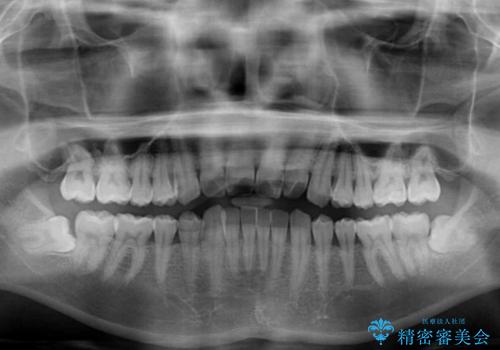

- 前歯のデコボコを気にして来院された患者様です。

主に下顎歯列全体の後方移動とIPR(歯と歯の間を削る)によってデコボコが解消するように設計し、インビザラインにより治療を行うこととしました。